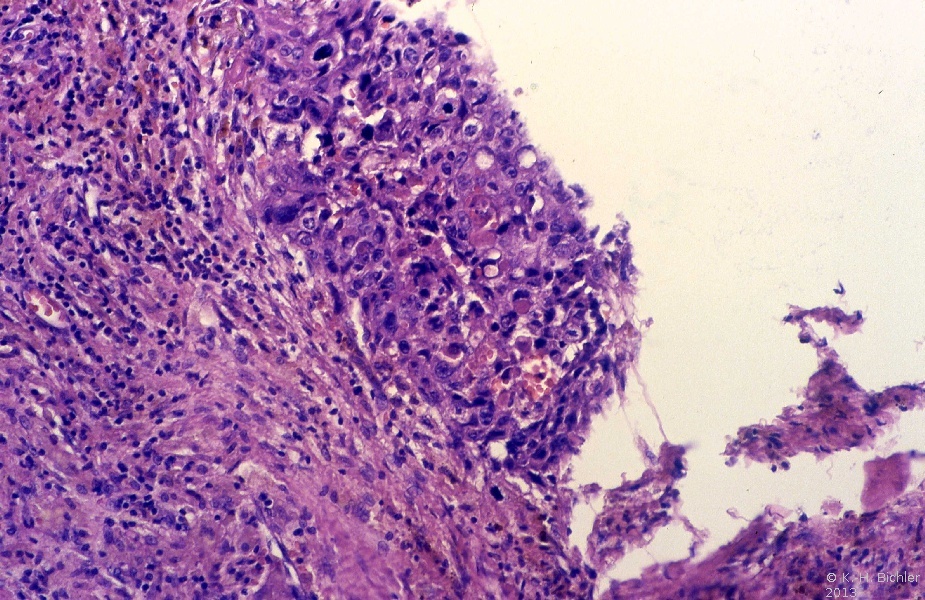

Die Abbildung zeigt den bei der Rezidivlymphadenektomie ausgeräumten Lymphknoten. Histologische ergab sich ein reifes Teratom und kleinere Anteile des embryonalen Karzinom (Abbildung 6).

Die histologische Untersuchung der Metastase ergab ein reifes Teratom und Anteile eines embryonalen Karzinoms mit Einbrüchen des Tumors in das Gefäßsystem (Abbildung 7)